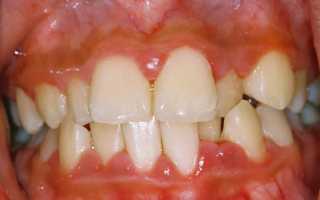

Гранулирующая форма болезни характеризуется существенным разрастанием десневой ткани, вследствие чего изменяется рельеф десны и наблюдается увеличение ее размеров. Изменяется и цвет десен, они приобретают ярко-красный оттенок. В результате отека и разрастания десневой ткани образуются ложные пародонтальные карманы, из которых может выделяться экссудат. При пальпации десны пациент отмечает болезненность ткани. Кровоточивость десен возникает при малейшем механическом, а изредка и при термическом, раздражении. Болезненность десен и их кровоточивость затрудняют прием пищи. Гранулирующая форма гипертрофического гингивита, как правило, является генерализованной, то есть поражение распространяется на десневую ткань, охватывающую большую группу зубов.

Фиброзная форма болезни также характеризуется уплотнением края десны, но при пальпации болевые ощущения отсутствуют. Цвет десен не меняется, а кровоточивость может полностью отсутствовать. Отечность десен приводит к искажению их контура, а течение фиброзного гипертрофического гингивита малоизменчивое.

Разрастание десневой ткани, характерное для третьей степени, достигает критических размеров, десневой край нависает над жевательной поверхностью зубов и их режущим краем. Изменяется рельеф десны, нарушается ее целостность. Поверхность десны покрывается кровоточащими грануляциями, которые очень болезненны и могут гноиться. Межзубные сосочки существенно увеличиваются в размерах и приобретают овальную форму.